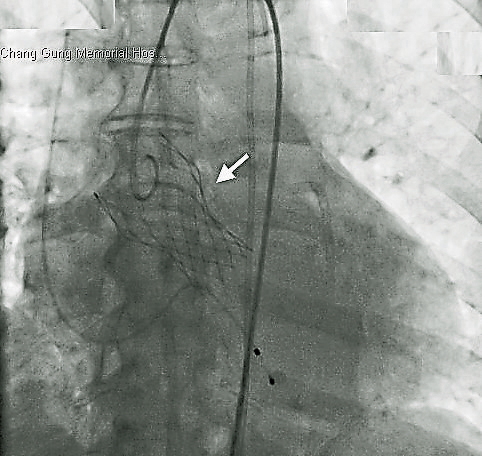

因此,在与病患及家属沟通之后,他们决定接受最近一项新的治疗方式,就是经导管主动脉瓣膜置放术(Transcatheter Valve Replacement,TAVR)。手术过程顺利并于一周内出院,也无发生任何并发症。目前,叶奶奶术后已于门诊定期追踪超过3年,一切健康顺利,家属也庆幸当初做了非常正确的决定。

主动脉瓣膜狭窄(Aortic Stenosis,AS)好发于长者,主要是因瓣膜退化钙化所造成。此类病患常会合并其他的共病,因此会增加在接受手术治疗时的风险。近年来发展出的TAVR治疗,迄今追踪的疗效与外科手术相当,但相对的风险较低,因此近年来已是此类手术高风险病患的首要治疗选择,甚至也渐渐被应用在手术中度风险的病患。

这项治疗仍有其风险及并发症,包括死亡丶中风丶心律传导阻断丶周边血管之并发症丶左心室或主动脉窦破裂等,然而一般而言仍比外科手术风险低。基于以上之风险,此类病患必需经内外心脏科医生联合会议讨论后认为适合者方可执行,而且必须在开刀房的混合手术室内操作,以便在发生紧急情况下,需要外科医生紧急介入治疗时可以马上进行,以增加病患接受此项治疗的安全性。因是较不侵入性之治疗,术后之恢复速度较传统手术为快,病患也较不辛苦,确是目前针对此类病患的最新且最好治疗方法。